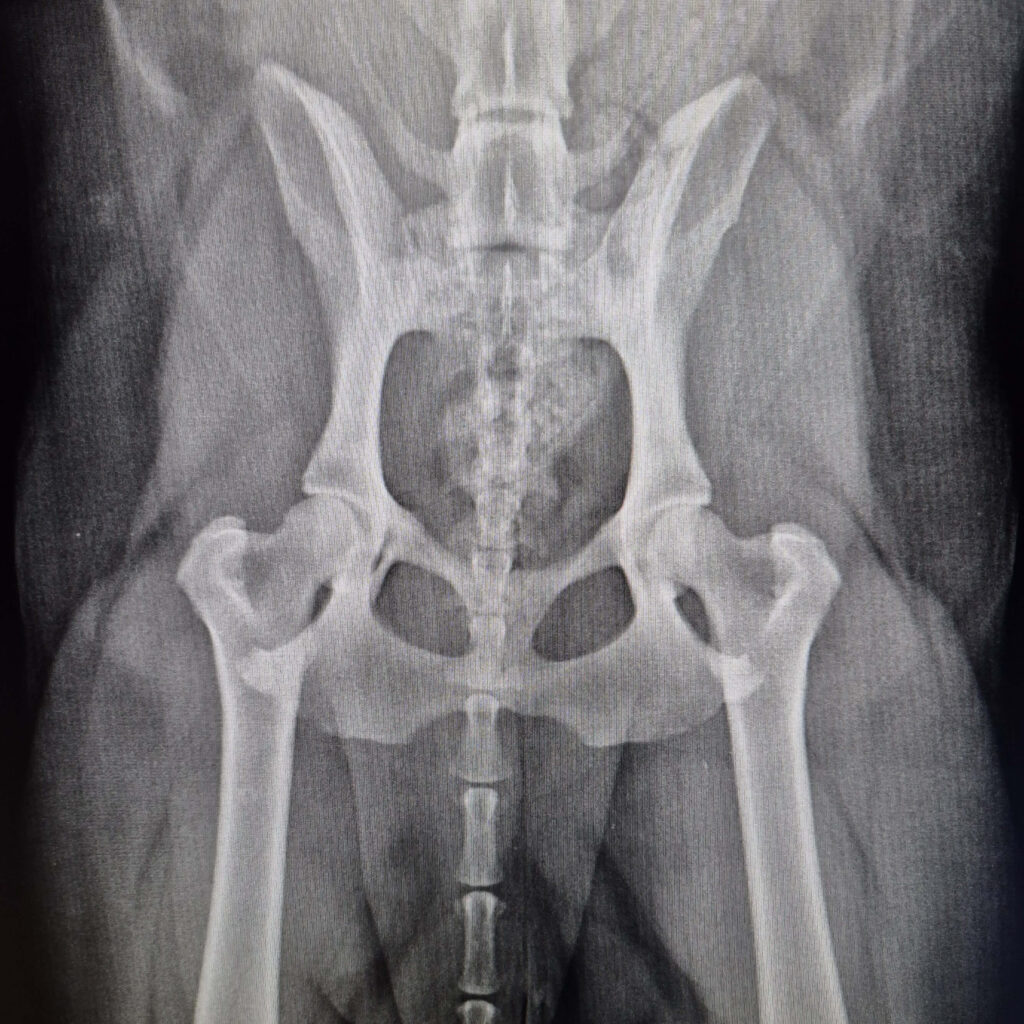

Como é feito o diagnóstico da Displasia Coxofemoral

A avaliação deve ser realizada por um ortopedista veterinário. Esse profissional tem a capacidade de interpretar os sinais clínicos de forma precisa, diferenciar doenças e solicitar exames específicos para chegar a um diagnóstico confiável.

A displasia pode variar em graus e apresentar particularidades em cada caso, por isso uma avaliação minuciosa é essencial.

Exames mais utilizados

O diagnóstico envolve alguns passos essenciais: avaliação clínica, com análise da marcha, palpação e testes ortopédicos específicos.

Raio-X, padrão ouro para identificar:

- Profundidade do acetábulo;

- Posicionamento da cabeça do fêmur;

- Alterações degenerativas;

- Instabilidade articular.

Em alguns casos, exames complementares como tomografia podem ser solicitados para planejamento cirúrgico.